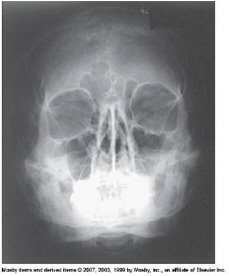

which projection best demonstrates the maxillary sinuses

parietoacanthial (waters)

where are the petrous ridges seen on an accurately positioned image of the parietoacanthial waters method projection of the paranasal sinuses

inferior to the floor of the maxillary sinuses

petrous pyramids